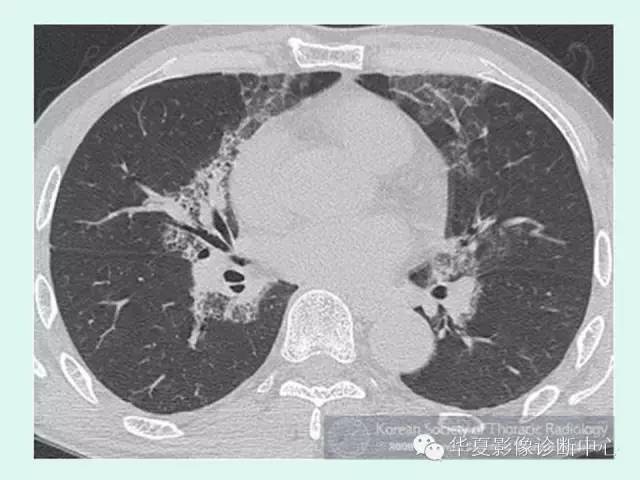

【病例】肺泡蛋白沉积症1例CT影像表现